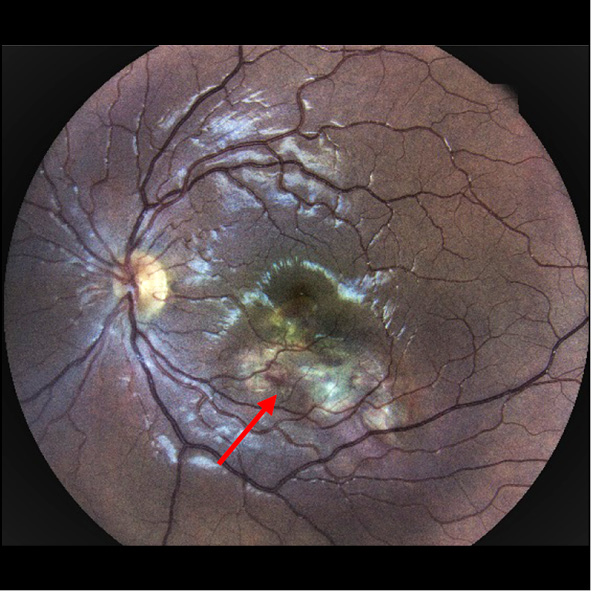

CNM was active in all children. The clinical presentation varied depending on the underlying disease. For example, a grayish subretinal focus with indistinct contours and perifocal hemorrhage, or without hemorrhage, was observed in the chorioretinal/choroidal focus area (Fig. 1). In addition, osteoma (Fig. 2) or hamartoma, and dystrophic changes in the macula in Best’s disease, were observed. Patients with myopia (Fig. 3) and idiopathic forms presented with isolated grayish or yellowish foci with indistinct contours and perifocal hemorrhage, or without it. Juxtapapillary CNM was characterized by the formation of a grayish proliferating focus adjacent to the optic disc (Fig. 4).

Fig. 4. Ophthalmoscopic image of subfoveolar active choroidal neovascularization in a child with optic disc drusen.